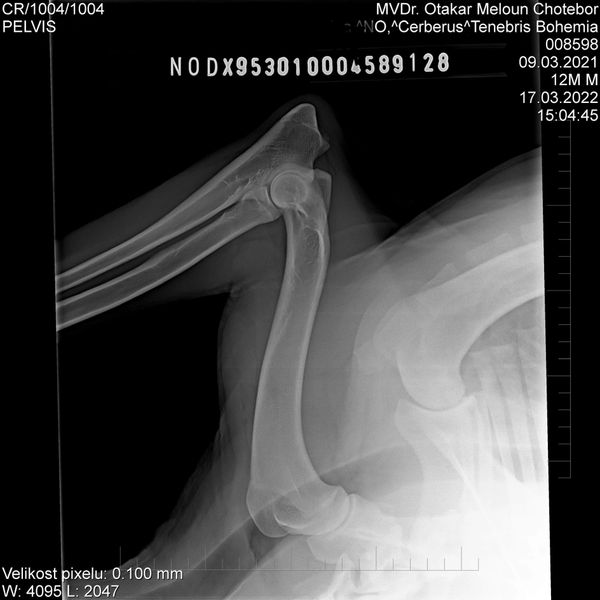

HD: A

ED: 0/0

Spondy: Free